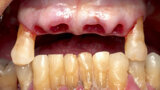

The fully digital Pro Arch protocol